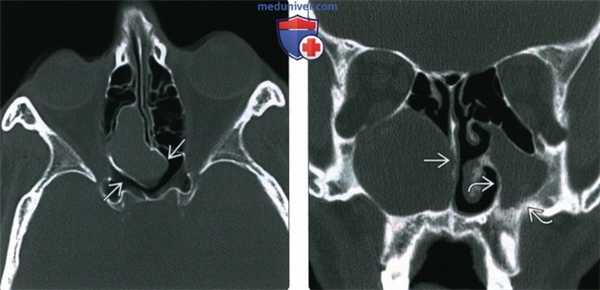

(Слева) При аксиальной «костной» КТ визуализируется заднее решетчатое мукоцеле, пролабирующее в основные пазухи, но не в орбиту. Определяется истончение и ремоделирование костей вокруг мукоцеле.

(Справа) При корональной «костной» КТ визуализируется крупное мукоцеле в правой верхнечелюстной пазухе (нетипичная локализация). Мукоцеле блокирует полость носа. Оцените изменения, обусловленные хроническим левосторонним гайморитом, - снижение объема пазухи и истончение стенок.